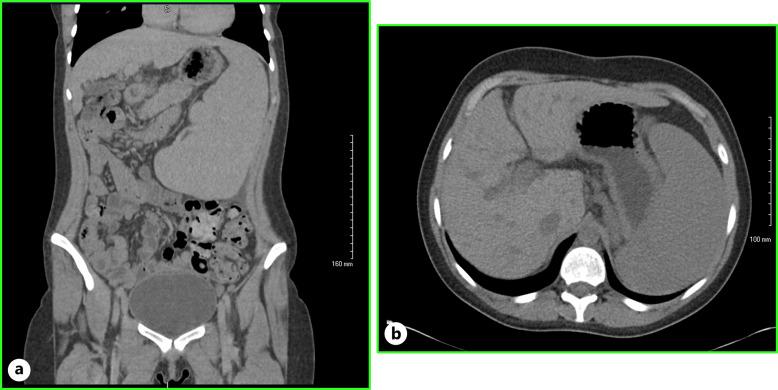

简介特纳综合征较少累及胃肠道系统。据报道,特纳综合征患者的肝脏病变是由非酒精性脂肪变性和脂肪性肝炎引起的,病毒性肝炎和酒精性肝炎则较为少见。门静脉高压通常与肝硬化有关,但也有一小部分患者在没有肝硬化的情况下也会出现门静脉高压。门静脉高压症在特纳综合征患者中非常罕见,在特纳综合征患者无肝硬化的情况下更少见:在此,我们报告了一例经肝活检证实的非肝硬化性门静脉高压症,其病因是门静脉血管病变:结论:临床高度怀疑可导致特纳综合征患者门静脉高压症的早期诊断和治疗,从而减轻门静脉高压症并发症的负担。

Case presentation: Herein, we report a case of liver biopsy-proven non-cirrhotic portal hypertension due to portosinusoidal vascular disease.